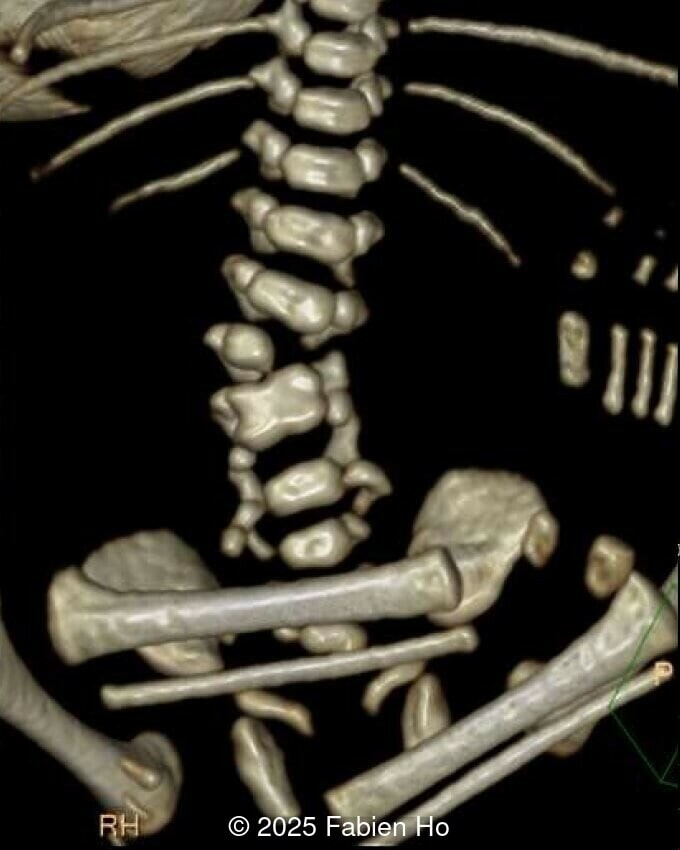

At 36 weeks gestation, the abdominal findings were unchanged however, the bones appeared short (<1st percentile) and the spine had an unusual appearance, therefore a computed tomography was performed at 37 weeks gestation.

Axial image of the fetal pelvis

Image 14 Axial image of the fetal pelvis

Our prenatal ultrasound revealed a male fetus with megabladder, dilation of both ureter and kidneys, and thinned kidney parenchyma consistent with Lower Urinary Tract Obstruction (LUTO).  Additional findings suspected on ultrasound and confirmed on computed tomography included:

• Dysostosis: Hemivertebrae L3, fused L4-L5, abnormal left foot with short metatarsals and missing phalanges